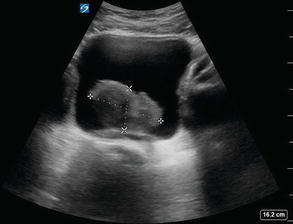

Böbrek ve mesaneden gelişen tümöral kitleler ultrason ve renkli doppler ultrason ile kolaylıkla saptanabilir. Renkli doppler inceleme ile olası kitlenin kanlanmasına bakılarak tanı açısından yardımcı olunabilir. Bu durumlarda ultrason eşliğinde böbrek kitlelerinden biyopsi yapılabilir.

Anne karnındaki bebeklerde ve yenidoğan döneminde bebeklerinin böbrek kanallarında genişlemeler saptanabilir. Bu durumda bebeğin belli aralıklarla kanal genişlemeleri kontrol edilir. Çok ilerlerse cerrahi olarak müdahale edilebilir. Bu durumun en sık sebepleri vezikoüreteral reflü ve postüretral valfdir.

Her hangi bir nedenle böbrek ve idrar kanallarında ciddi tıkanıklık ve genişleme olan hastalarda böbrek fonsiyonlarını bozmamak için ultrason eşliğinde peruktan nefrostomi dediğimiz işlem ile böbrek içerisine katater yerleştirilir ve bu katater aracılığı ile idrar drenajı dışarıya yapılabilir.